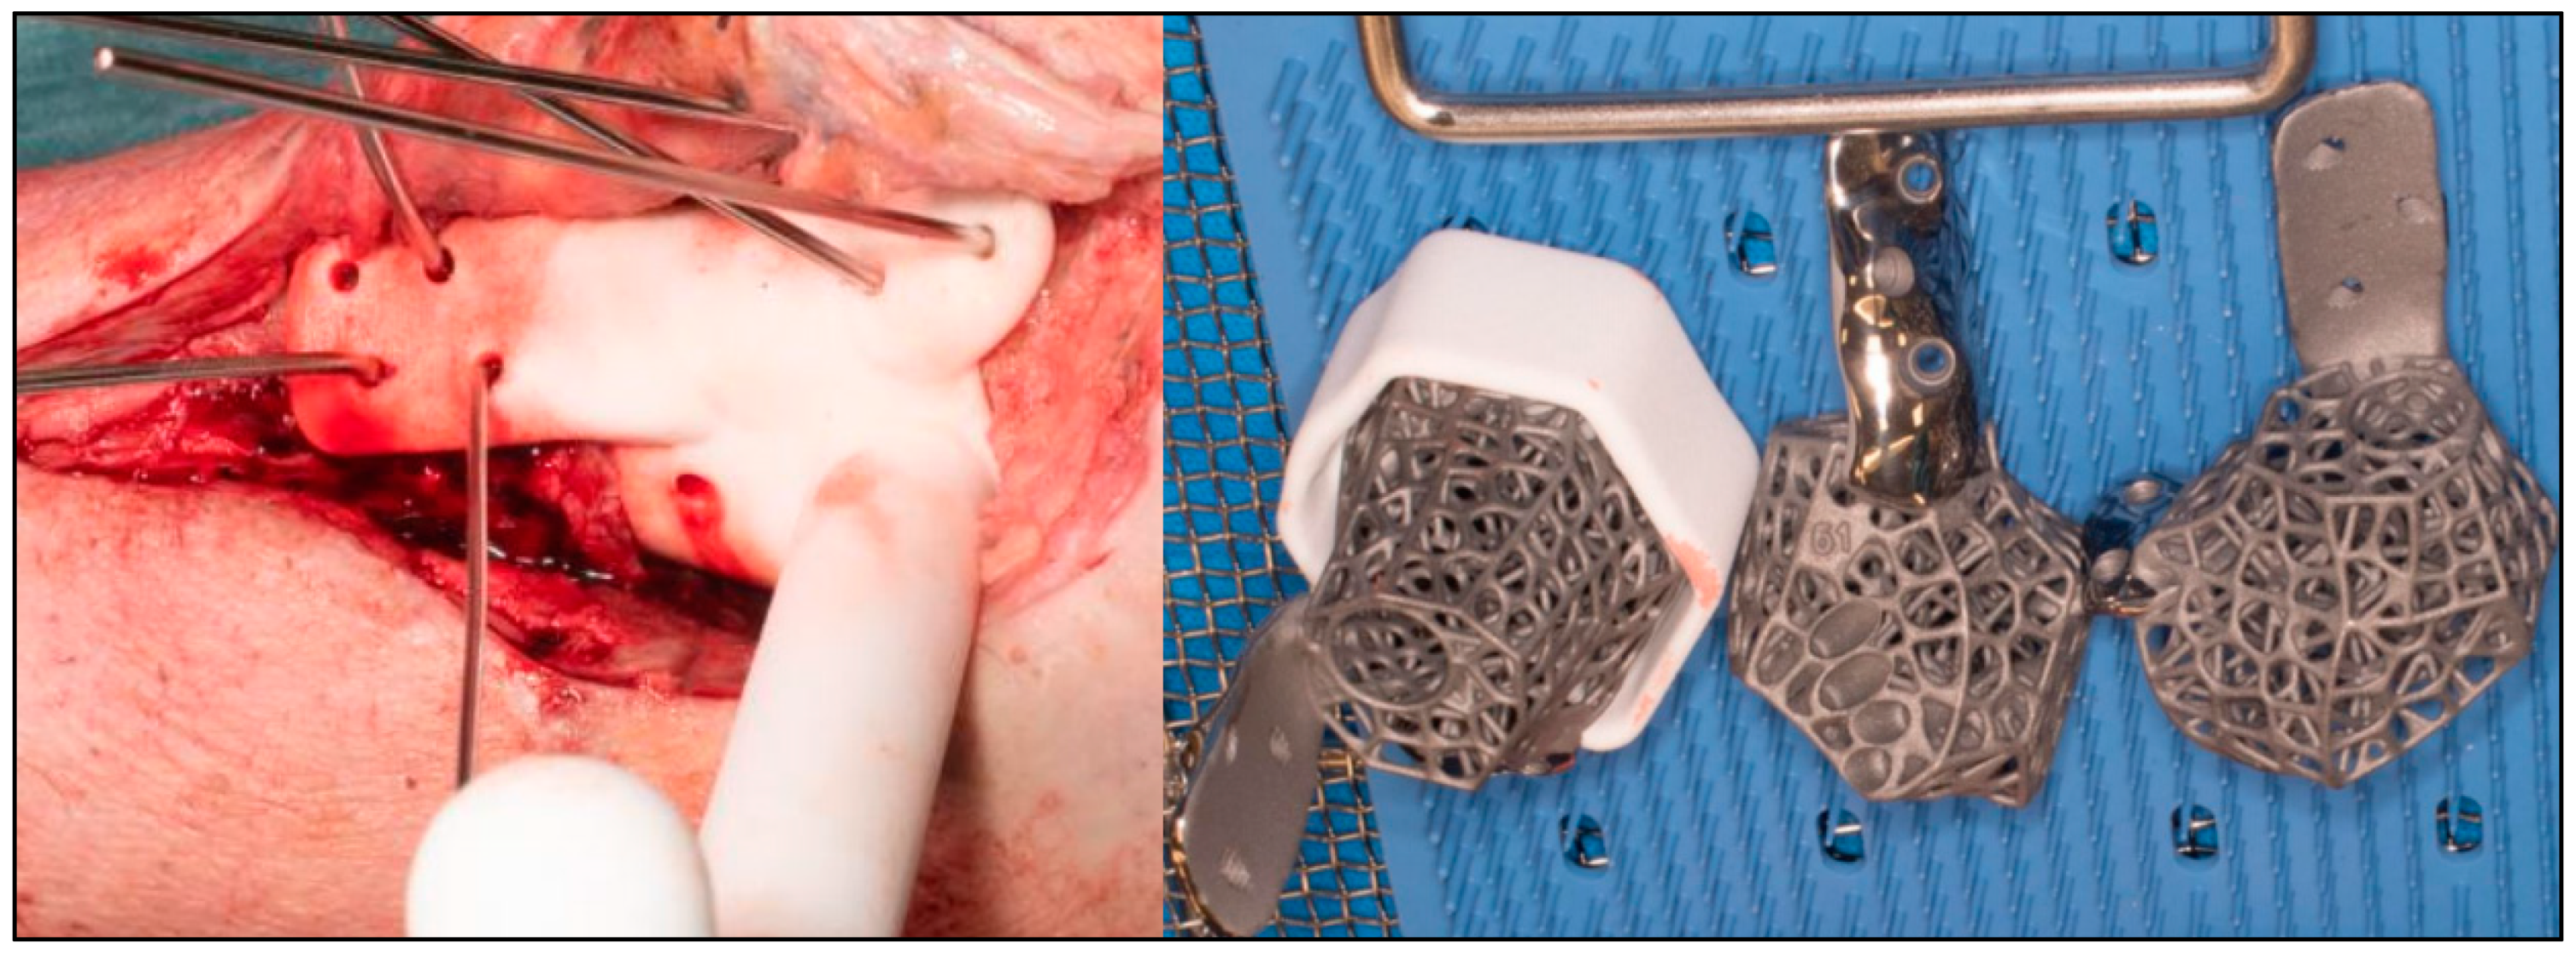

2.2. Surgical Technique